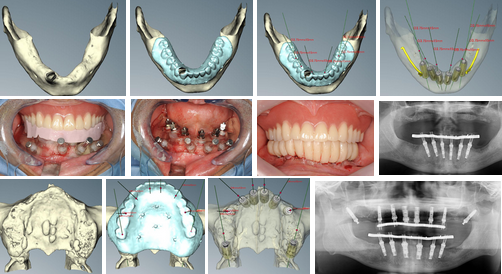

4年前からノーベル・バイオケア社のNobelGuideによるコンピュータ・ガイディッド・サージェリー(Computer-guided surgey: コンピュータにてインプラント治療計画を立て、その通りに手術が可能になる手術法)にて低侵襲でかつ短時間の治療が可能となった。

しかし、上顎では上顎洞(上顎骨にある空洞で副鼻腔の一つ)との関係で骨量が少ない症例が多く、グラフトレス(graftless: 骨造成をしないという意味)では対応できず、最低限度のグラフト(graft: 骨造成をするという意味)を行う必要があり、当院ではそれを行うことにより、上顎無歯顎症例の96%に即時荷重を可能にしている。

4年前からノーベル・バイオケア社のNobelGuideによるコンピュータ・ガイディッド・サージェリー(Computer-guided surgey: コンピュータにてインプラント治療計画を立て、その通りに手術が可能になる手術法)にて低侵襲でかつ短時間の治療が可能となった。

しかし、上顎では上顎洞(上顎骨にある空洞で副鼻腔の一つ)との関係で骨量が少ない症例が多く、グラフトレス(graftless: 骨造成をしないという意味)では対応できず、最低限度のグラフト(graft: 骨造成をするという意味)を行う必要があり、当院ではそれを行うことにより、上顎無歯顎症例の96%に即時荷重を可能にしている。

<グラフトレス症例>

<グラフト症例1(上顎前歯部骨移植)>

<グラフト症例2(両側サイナスリフト)>